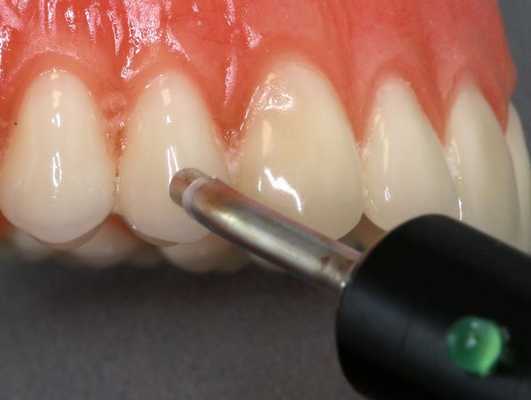

Диагностика периодонтита проводится на основании жалоб пациента, анамнеза заболевания, оценки общесоматического статуса, осмотра головы и шеи, полости рта, зуба, его перкуссии, зондирования и термопробы, электроодонтодиагностики (ЭОМ) и рентгенологического исследования. [10]

ЭОМ — это метод стоматологического исследования, основанный на определении порогового возбуждения болевых и тактильных рецепторов пульпы зуба при прохождении через неё электрического тока.

Важно! Метод диагностики, основанный на использовании электрического тока, позволяет определить болевой порог пульпы зуба для определения ее жизнеспособности и уровня поражения.

Также для постановки диагноза используются легкие механические манипуляции — постукивания в нескольких положениях (позволяют точно определить пораженный канал). Также возможно использование холодового теста.